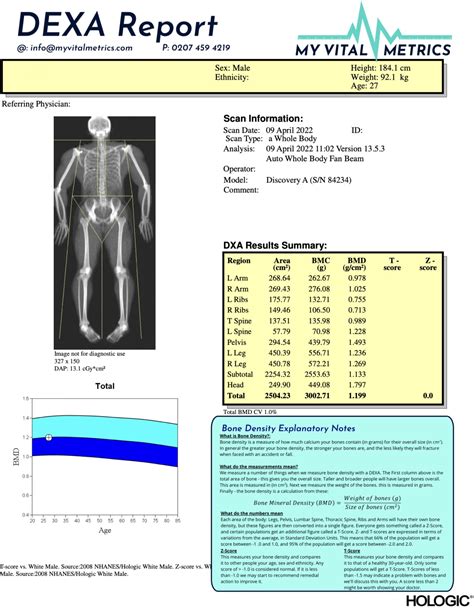

Dexa Scan Report Template